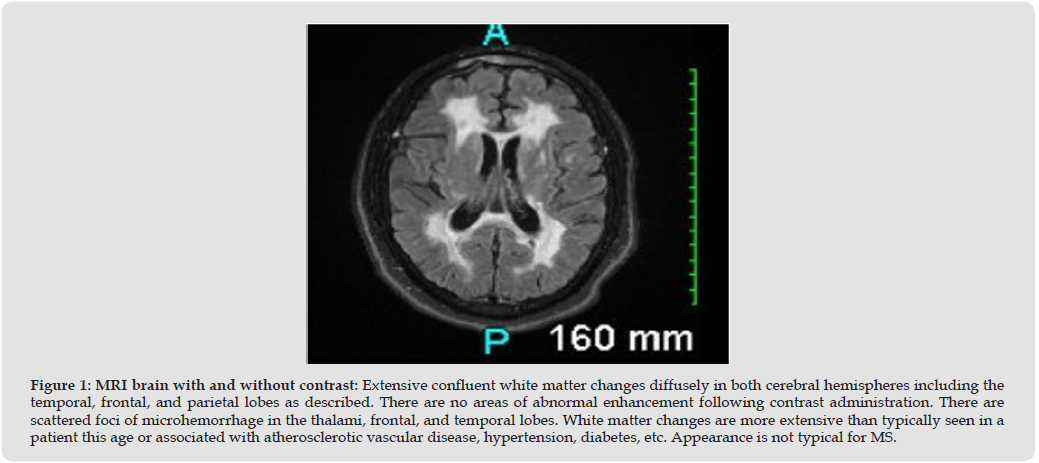

We report a case of a 49-year-old man who presented to the emergency department (ED) with headache for 3 days duration and no imaging was performed in ED. He later referred to the neurology clinic and upon further evaluation, he revealed having episodes of numbness, fatigue, vertigo, confusion, weakness, dizziness, memory loss, imbalance, blurring vision and difficulty in walk for the past 10- 15 years. He was previously told by a neurologist that his brain MRI results were abnormal, but he did not follow up. We ordered an MRI (Magnetic Resonance Imaging) which widespread and significant white matter lesions (Figures 1, 2A & 2B) suggestive of Cerebral Autosomal Dominant Arteriopathy with Subcortical Infarcts and Leukoencephalopathy (CADASIL). The white matter lesions were so extensive that they closely disguised as tumfactive multiple sclerosis or brain lesions. It is diagnosed by genetic testing for NOTCH3 gene, which was positive in this patient. Currently, there are no specific treatments are available for this disorder and he was managed with symptomatic management for his migraine headache, memory loss, and muscle weakness reducing mortality and morbidity.